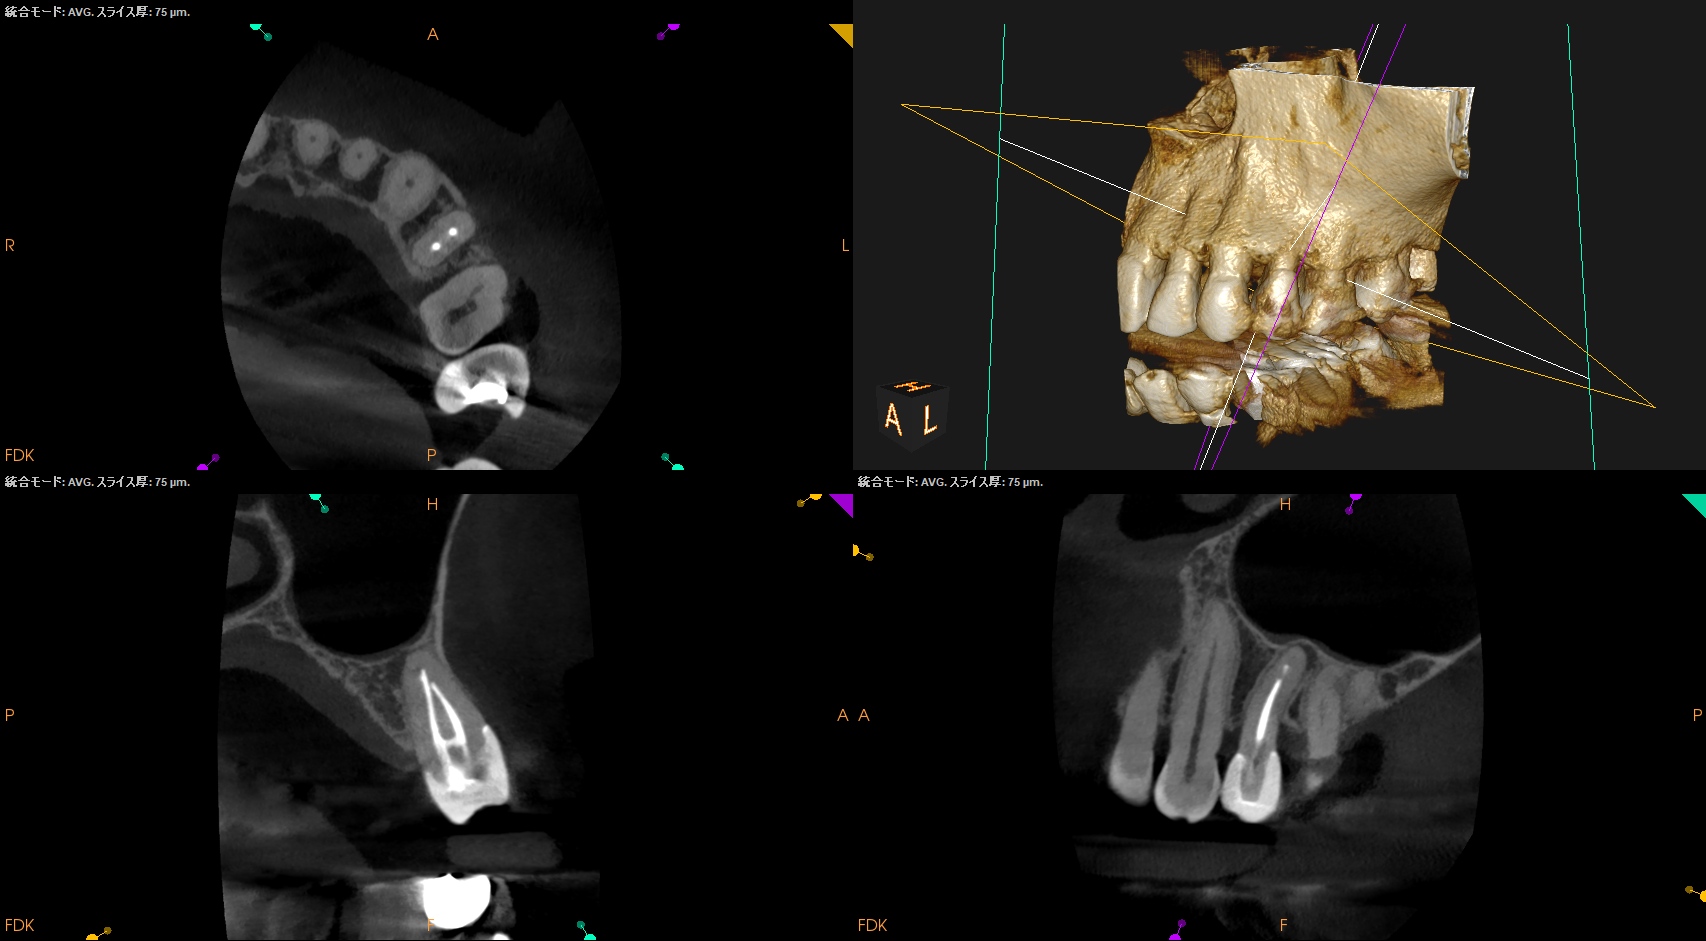

CBCT(2025.8.22)

#13 遠心のマージンが歯肉縁下でクラウンが不適合だ。ここにものが詰まるようだ。

これが患者さんの主訴である。

また、根尖病変があり根管形成・根管充填が太くなされていることからApicoectomyへ移行することになった。

#13 Apicoectomy(2025.10.7)

術後にPA, CBCTを撮影した。

問題はないだろう。